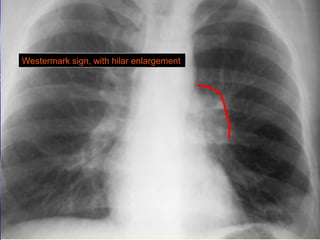

 DDeeccrreeaasseedd vvaassccuullaarriittyy iinn tthhee ppeerriipphheerraall lluunngg ((WWeesstteerrmmaarrkk

ssiiggnn((..

 EEnnllaarrggeemmeenntt ooff tthhee cceennttrraall ppuullmmoonnaarryy aarrtteerryy ((FFlleeiisscchhnneerr

WWeesstteerrmmaarrkk’’ss ssiiggnn

Westermark sign, with hilar enlargement

Radiographic ssiiggnnss ooffaaccuuttee ppuullmmoonnaarryy eemmbboolliissmm SSiiggnnss wwiitthh rreellaattiivvee hhiigghh ssppeecciiffiicciittyy bbuutt llooww sseennssiittiivviittyy ffoorr aaccuuttee ppuullmmoonnaarryy eemmbboolliissmm::  DDeeccrreeaasseedd vvaassccuullaarriittyy iinn tthhee ppeerriipphheerraall lluunngg ((WWeesstteerrmmaarrkk ssiiggnn((..  EEnnllaarrggeemmeenntt ooff tthhee cceennttrraall ppuullmmoonnaarryy aarrtteerryy ((FFlleeiisscchhnneerr ssiiggnn((..  PPlleeuurraall bbaasseedd aarreeaass ooff iinnccrreeaasseedd ooppaacciittyy ((HHaammppttoonn hhuummpp((..  HHeemmiiddiiaapphhrraaggmm eelleevvaattiioonn.. NNoonn ssppeecciiffiicc ssiiggnnss aassssoocciiaatteedd wwiitthh aaccuuttee ppuullmmoonnaarryy eemmbboolliissmm tthhaatt mmaayy bbee aassssoocciiaatteedd wwiitthh ootthheerr ddiisseeaasseess::  FFooccaall aarreeaa ooff iinnccrreeaasseedd ooppaacciittyy..  LLiinneeaarr aatteelleeccttaassiiss..  PPlleeuurraall eeffffuussiioonn..

Westermark sign, withhilar enlargement